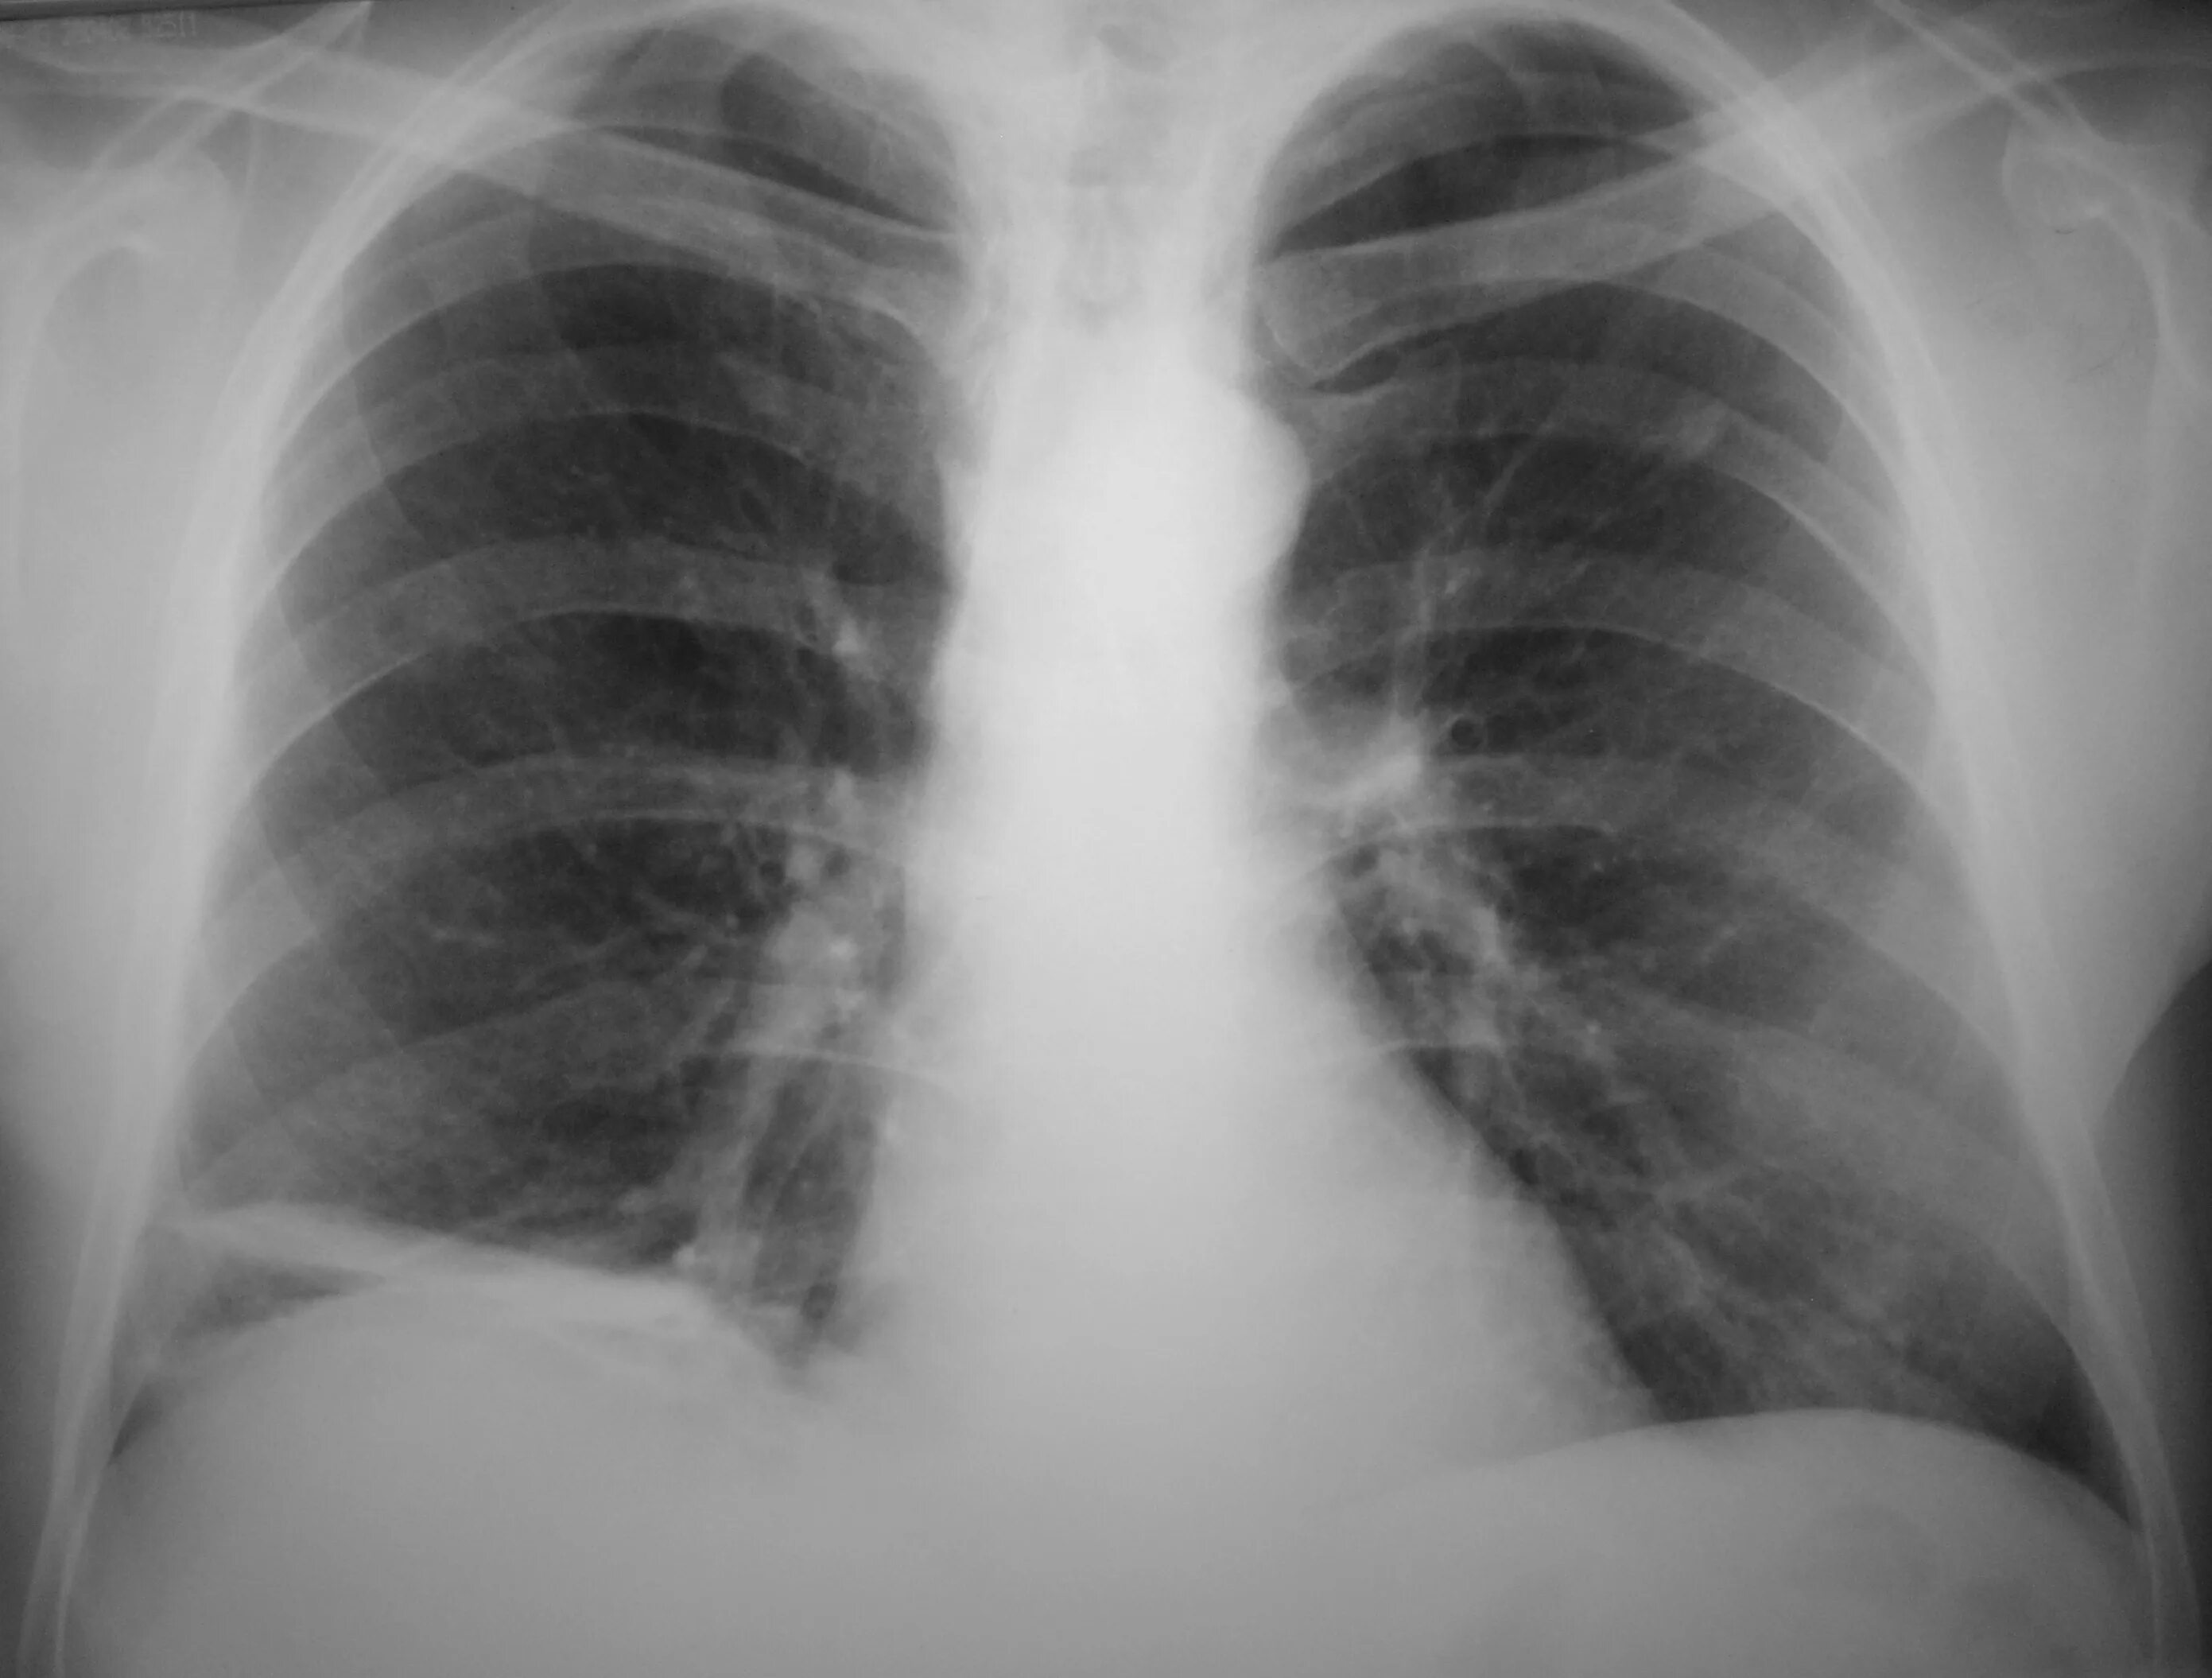

Умеренный пневмосклероз